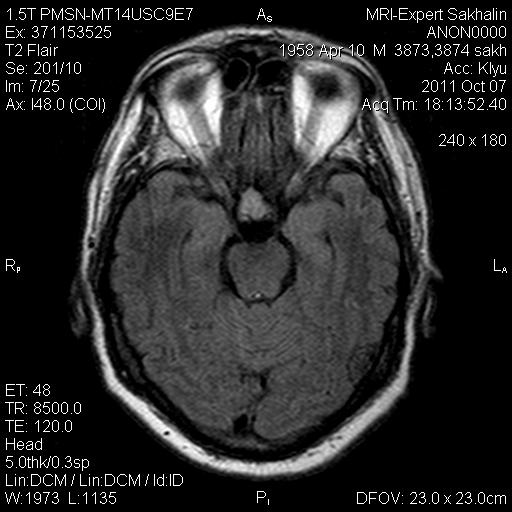

Аденома гипофиза

Вот такая аденома гипофиза сегодня.Мужчина с жалобами на снижение зрения.

Публикации: 175

Мне кажется что это все же не аденома, может глиома хиазмы ? (воронки гипофиза)? Или еще какое-нибудь объемное образование.... Что то меня смущает, еще не поняла что, но В любом случае наверное я бы однозначно не писала что это аденома, а выставила бы весь диф. ряд.

Танюша, обычно пишем "образование хиазмально-селлярной области"

Присоединяюсь к последнему коментарию, все таки откуда растет по моему мнению трудно однозначно сказать, лучше себя обезопасить написав "объемное образование хиазмально-селлярной области"